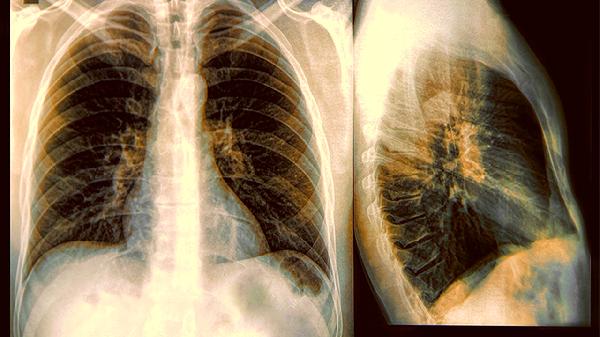

五、抗肿瘤靶向药物

抗肿瘤靶向药物是针对特定基因突变设计的精准治疗药物,主要用于驱动基因阳性的晚期非小细胞肺癌等肺部恶性肿瘤。例如,吉非替尼片适用于表皮生长因子受体基因具有敏感突变的局部晚期或转移性非小细胞肺癌;克唑替尼胶囊可用于间变性淋巴瘤激酶阳性的局部晚期或转移性非小细胞肺癌;奥希替尼片则用于表皮生长因子受体酪氨酸激酶抑制剂治疗时或治疗后出现疾病进展,并且经检测确认存在表皮生长因子受体突变阳性的患者。这类药物需在基因检测指导下使用,并密切监测肝肾功能及可能出现的间质性肺病等严重不良反应。